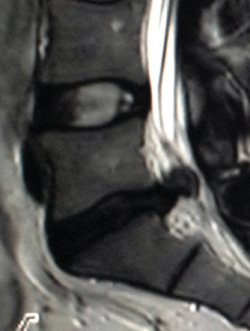

Resonancia magnética(19,21,24)

Ofrece una excelente definición de las estructuras blandas (tanto intra- como extrarraquídeas). Permite una buena visualización del saco dural y su contenido, sin la necesidad de tener que inyectar contraste intratecal, además de permitir la detección de patologías intramedulares. Es, por tanto, la técnica diagnóstica de elección ante la sospecha de una patología específica de partes blandas, discos intervertebrales, ligamentos y saco neural, así como en la evaluación de una posible afectación tumoral, infecciosa o metabólica del raquis vertebral lumbar (Figura 13).

Figura 13. Hernia de disco extruida.

Las principales indicaciones para el empleo de esta técnica en el estudio de la patología dolorosa lumbar serían:

- La sospecha clínica de hernia discal: de elección, especialmente en pacientes jóvenes sin signos de espondilosis ni estenosis del canal vertebral; debería reservarse para pacientes candidatos a un tratamiento quirúrgico o aquellos que, con síntomas o signos de radiculopatía, no responden adecuadamente al tratamiento conservador pautado durante un periodo variable de 4 a 6 semanas.

- La valoración del dolor lumbar tras una cirugía vertebral discal: constituye el único método diagnóstico para diferenciar una cicatriz fibrosa por una probable fibrosis posquirúrgica de una recidiva herniaria, con una precisión cercana al 98%.